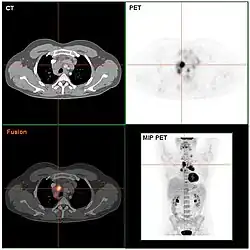

De diagnose wordt gesteld met behulp van microscopisch onderzoek (meestal door meerdere, ervaren pathologen) van een door een chirurg verwijderde lymfeklier (lymfeklierextirpatie). Onder de microscoop wordt bij de ziekte van Hodgkin de typische reed-sternbergcel (RS-cel) gevonden. Hiermee onderscheidt de ziekte zich van alle andere soorten lymfeklierkanker die de verzamelnaam non-hodgkinlymfoom hebben gekregen. De prognose van de ziekte wordt vooral bepaald door het stadium en het subtype van de ziekte. Op grond van een stadiëringsonderzoek worden vier stadia (I t/m IV) onderscheiden naarmate de ziekte zich verder door het lichaam heeft verspreid. Dit onderzoek omvat o.a. een computertomografie, waarbij alle lymfeklieren in de buik- en de borstholte worden afgebeeld, en een beenmergonderzoek.

Stadiëring

Nadat een patiënt is gediagnosticeerd met de ziekte moet het stadium worden bepaald. Ann Arbor-stadiëring is het stadiëringssysteem dat wordt gebruikt bij het bepalen van het stadium voor de ziekte.